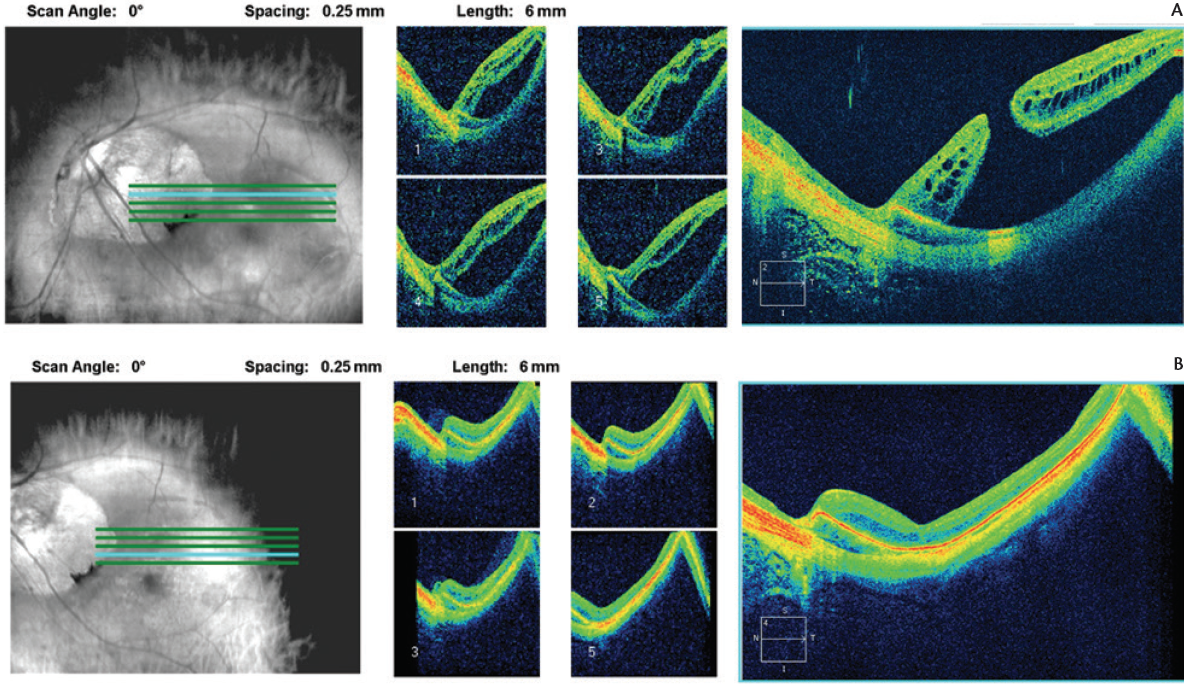

In addition, challenges associated with surgery in high myopia include long axial length; staphyloma (Figure, A); and, in some eyes, decreased contrast due to light pigmentation.

Figure. Preoperative optical coherence tomography (OCT) of a macular hole associated with a posterior pole detachment in a patient with high myopia and staphyloma (A). Postoperative OCT of the same eye indicates that the macular hole is closed, subretinal fluid is pumped out by the retinal pigment epithelial cells, and the retina is reattached (B).

In eyes with high myopia and staphyloma, if there are no peripheral breaks, after the fluid-air exchange the residual fluid may collect posteriorly. Draining this fluid through the break may risk enlarging the hole or touching the photoreceptors due to the compromised view. This fluid does not have to be drained, and can be left behind. Healthy retinal pigment epithelial cells will pump the fluid out of the subretinal space, as long as the hole is closed (Figure, B). This process is slow and sometimes can take a few months.